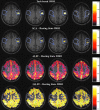

The aim of this study was to explore whether the phenomenon of brain tumor-related neurovascular uncoupling (NVU) in resting-state blood oxygen level-dependent functional magnetic resonance imaging (BOLD fMRI) (rsfMRI) may also affect the resting-state fMRI (rsfMRI) frequency domain metrics the amplitude of low-frequency fluctuation (ALFF) and fractional ALFF (fALFF). Twelve de novo brain tumor patients, who underwent clinical fMRI examinations, including task-based fMRI (tbfMRI) and rsfMRI, were included in this Institutional Review Board-approved study. Each patient displayed decreased/absent tbfMRI activation in the primary ipsilesional (IL) sensorimotor cortex in the absence of a corresponding motor deficit or suboptimal task performance, consistent with NVU. Z-score maps for the motor tasks were obtained from general linear model analysis (reflecting motor activation vs. rest). Seed-based correlation analysis (SCA) maps of sensorimotor network, ALFF, and fALFF were calculated from rsfMRI data. Precentral and postcentral gyri in contralesional (CL) and IL hemispheres were parcellated using an automated anatomical labeling template for each patient. Region of interest (ROI) analysis was performed on four maps: tbfMRI, SCA, ALFF, and fALFF. Voxel values in the CL and IL ROIs of each map were divided by the corresponding global mean of ALFF and fALFF in the cortical brain tissue. Group analysis revealed significantly decreased IL ALFF (p = 0.02) and fALFF (p = 0.03) metrics compared with CL ROIs, consistent with similar findings of significantly decreased IL BOLD signal for tbfMRI (p = 0.0005) and SCA maps (p = 0.0004). The frequency domain metrics ALFF and fALFF may be markers of lesion-induced NVU in rsfMRI similar to previously reported alterations in tbfMRI activation and SCA-derived resting-state functional connectivity maps.